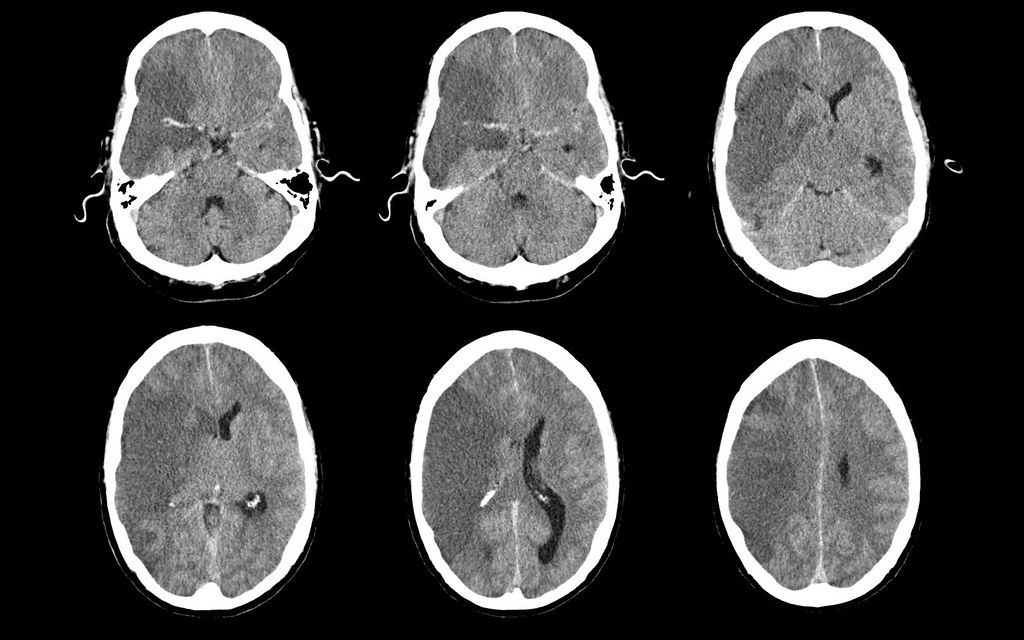

Old Infarct Ct Radiology . Ct perfusion in ischemic stroke has become established in most centers with stroke services as an important adjunct, along with ct. The overall sensitivity of ct to diagnose. This image shows the typical. Ct angiography (cta) and perfusion ct may be performed immediately after unenhanced ct. This ct shows the typical appearance of an old territorial infarct. Normal grey and white matter is replaced by tissue of similar density to. Several months after an acute ischaemic event the brain cells in the infarcted area have died leaving an area of low density. Cta and perfusion ct allow better identification of infarct, vessel.

Cta and perfusion ct allow better identification of infarct, vessel. Ct angiography (cta) and perfusion ct may be performed immediately after unenhanced ct. Several months after an acute ischaemic event the brain cells in the infarcted area have died leaving an area of low density. The overall sensitivity of ct to diagnose. This ct shows the typical appearance of an old territorial infarct. Ct perfusion in ischemic stroke has become established in most centers with stroke services as an important adjunct, along with ct. This image shows the typical. Normal grey and white matter is replaced by tissue of similar density to.

Old Infarct Ct Radiology Ct perfusion in ischemic stroke has become established in most centers with stroke services as an important adjunct, along with ct. This image shows the typical. Several months after an acute ischaemic event the brain cells in the infarcted area have died leaving an area of low density. Cta and perfusion ct allow better identification of infarct, vessel. Ct angiography (cta) and perfusion ct may be performed immediately after unenhanced ct. Normal grey and white matter is replaced by tissue of similar density to. The overall sensitivity of ct to diagnose. Ct perfusion in ischemic stroke has become established in most centers with stroke services as an important adjunct, along with ct. This ct shows the typical appearance of an old territorial infarct.